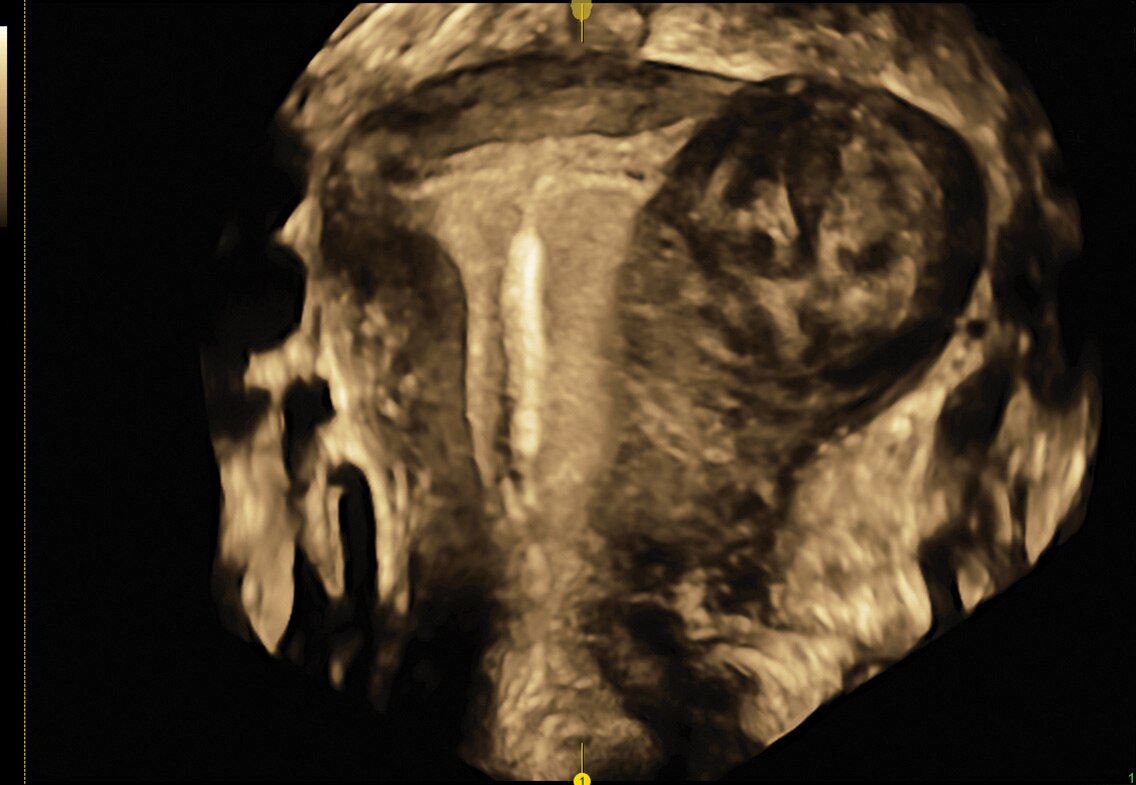

HDlive

Obtenha facilmente imagens de volume com profundidade e clareza sem precedentes usando o conjunto de tecnologia HDlive™, uma ferramenta essencial para a solução de problemas.